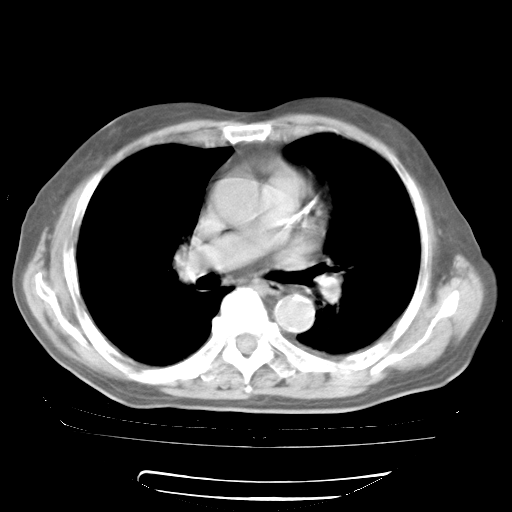

今天部分检查

轻微咳嗽,无痰,(体温正常时)R20次/分,P75次/分,双肺底、腋下可闻及少量捻发音。下肢轻度浮肿。

血常规:白细胞9.11×109/L,N0.92,L5.64,血小板39.2×109/L,HB148g/L,ESR2mm/H。

尿常规:潜血+

血生化:总蛋白69.71g/L,白蛋白38.40g/L,球蛋白31.31g/L,CRP27.9mg/L,尿素氮11.98mmol/L,肌酐106μmol/L,乳酸脱氢酶1099 U/L,肌酸激酶108U/L,CK-MB 61U/L。

腹部B超:胆囊壁增厚,肝、胆、胰、脾、肾无异常,肠系膜淋巴结、腹膜后淋巴结无增大。

ECG:右心室增大

心脏超声检查:无右心室增大。

增加治疗:异烟肼、利福平、乙胺丁醇,静滴左氧氟沙星、参麦注射液。甲强龙从80mg暂减为40mg。

强的松3月1日改为10mg qd,4月1日改为10mg qod。3月份以前的减量过程和环磷酰胺疗程需等明天查看记录(我岳父自己做的记录在他家里)。